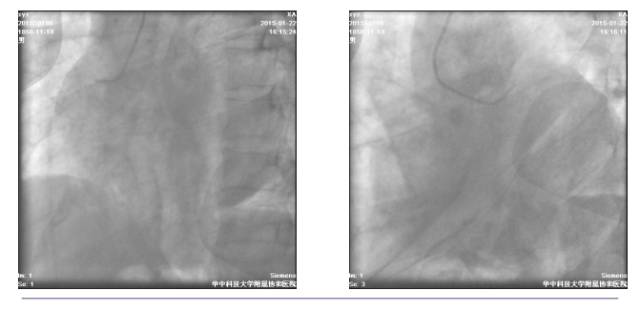

冠脉造影检查+急诊PCI

◆16:15 右冠状动脉造影:右冠近端轻度狭窄,第二屈膝部中段狭窄约50%

◆16:16 蜘蛛位造影示左主干中段以远急性闭塞

◆16:20 BMW导丝通过病变到达前降支远端

◆16:22 2.0×20mm Tazuna球囊扩张后退回左主干,显示左主干体部至末端高度狭窄并血栓

◆16:34 球囊扩张后于左主干起始部-前降支近端植入4.0×18mm Partner支架一枚,并与回旋支近端行对吻

◆16:35 PCI术后(肝位)

◆16:36 PCI术后(头位)